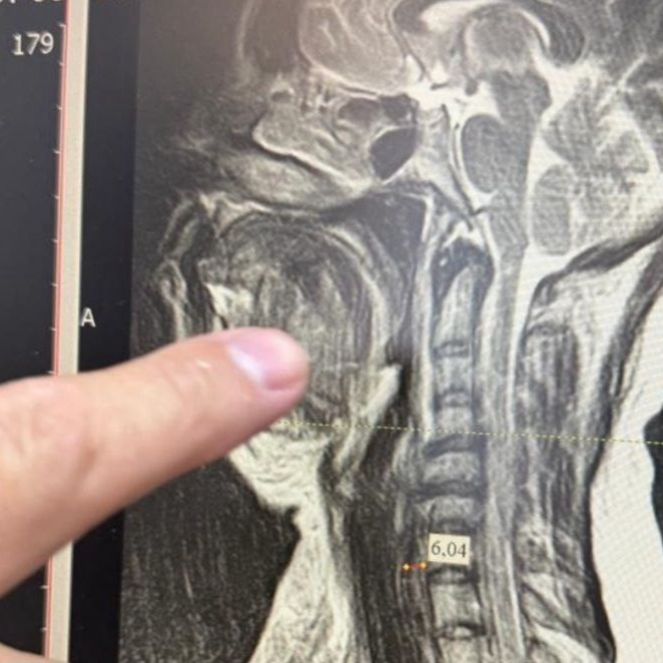

Медики столкнулись с одной из самых сложных форм осложнения – двусторонней флегмоной окологлоточного пространства, которая при отсутствии своевременного лечения в большинстве случаев заканчивается летальным исходом. Специалисты стали готовить женщину к экстренной операции. Из-за сильного отека тканей шеи невозможно было вставить трубку для дыхательного наркоза, поэтому работали через трахею.

Челюстно-лицевой хирург Шахбан Мисриев установил около восьми дренажей. Три дня пациентка провела в реанимационном отделении, подключенной к аппарату ИВЛ.